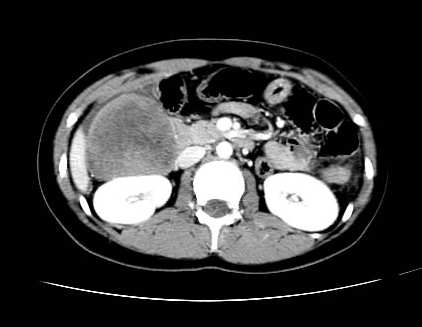

女 16岁  右上腹痛一天,无其他不适

肿块最大径位于十二指肠降段与水平段移行处,并且与肝脏压迹呈“0”形征,可以考虑位于肝外并与胃肠道关系紧密,考虑胃肠道间质瘤(gist)可能较大,须除外神经节起源肿瘤。

肿块与十二指肠关系密切,支持间质瘤诊断.肝脏与结肠均为受压改变.

右下腹巨大肿快,密度不均匀,内见坏死低密度区,边界清楚,与周边胀器明显有分界,未见强化,多考虑来源于间叶组织的良性肿物.

我坚决反对您的观点,该病例定位:横结肠肝曲与升结肠之间的肠系膜及部分肠壁。请看下图:

病灶巨大,少部分向肠腔内生长,大部分向长腔外生长。其密度不均匀,增强显示明显不均匀强化,并见有大片状始终不强化的不规则坏死液化区。虽然病灶中上部形态尚可,病人又如此年轻,但中下部形态、密度、强化特点强烈提示为恶性病灶。综上,我考虑本病例为:恶性胃肠道间质瘤。